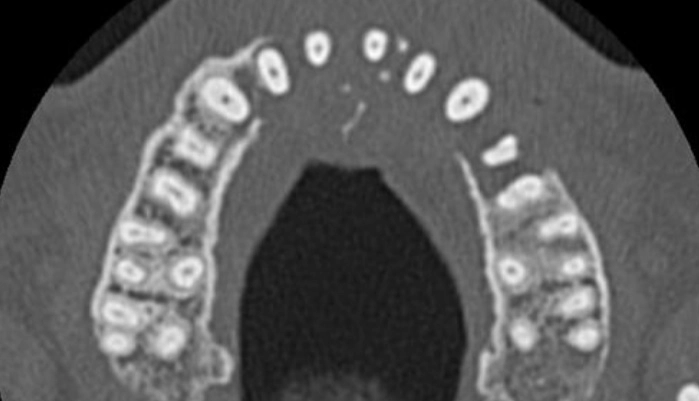

치료비가 저렴한 현지 치과를 찾은 그는 엑스레이 촬영 결과 충격적인 소식을 접했다. 왼쪽 위턱뼈가 보이지 않는다는 진단을 받은 것이다.

정밀 CT 촬영 결과 그의 부비동에서 자라난 종양이 코 아래까지 퍼져 있는 것이 확인됐다.

이미 종양은 그의 위턱뼈를 ‘먹어 치운’ 상태였으며 목까지 전이되기 시작한 상태였다.